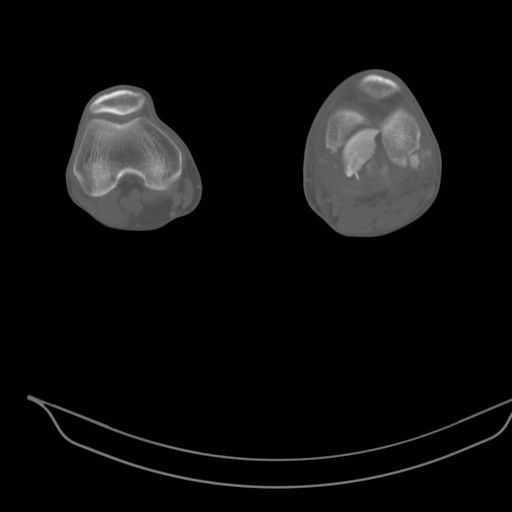

При внутрисуcтавных переломах трехмерные (3D) изображения, кроме красивого снимка, не дают полную информацию о состоянии отломков, самыми информативными являются корональные срезы на КТ и обычная длинная ренгенограмма конечности для сравнения оси конечности.

Фронтальные внутрисуставные переломы мыщельков бедра, так называемые Hoffa fracture, не частые, но встречающиеся переломы, в основном они связаны с травмой высокой энергией.

В зависимости от смещения рекомендуется сопоставление костных фрагментов с последующей жесткой фиксацией.

В вашем случае доступ будет медиальный, сопоставить развернутый медиальный мыщелок и фиксацию надо произвести в передне-заднем

направлении шурупами 4.5 мм в диаметре, углубив головку шурупов под хрящ, а поперечную фиксацию - межмыщелковыми шурупами. Желательно применить шурупы 6.3 мм в диаметре. Дополнительная Buttress technique пластина предотвратит перелом от скольжения.

Даже при сросшемся переломе мыщелка рекомендуется реконструктивная операция для предотвращения последующих варус или вальгус деформации.

Место образовавшего костного дефекта после разворота мышелка заполняется спонгиозной аутокостью. Костная пластика применяется даже

в свежем случае.

Под наркозом редрессация, ранняя разработка сустава после операции, нагрузка на конечность через 12 недель помогут удержать без коллапса

фиксацию и поможет больному восстановить функции конечности без артропластики коленного сутава.